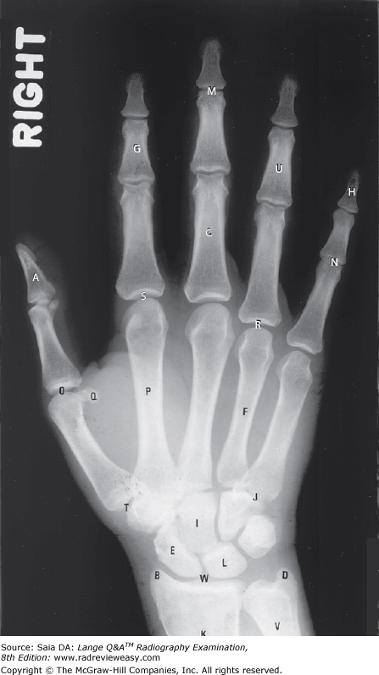

What is the structure labeled number 5 in Figure 2–37?

A Trapezium B Scaphoid C Ulnar styloid D Radial styloid

Radial styloid

Which of the following correctly identifies the letter T in the radiograph shown in Figure 7–13?

Diarthrotic joint

Which of the following correctly identifies the letter L in the radiograph shown in Figure 7–13?

Lunate

What is the structure labeled number 2 in Figure 2–37?

Trapezium

Which of the following correctly identifies the radial styloid process in the illustration in Figure A?

Number 11